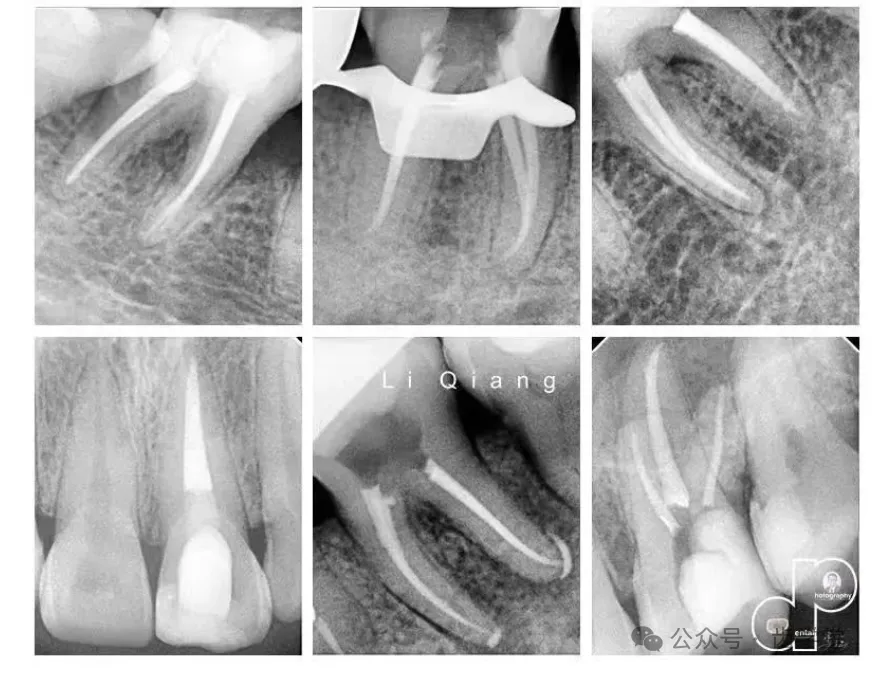

4. 热牙胶垂直加压充填术与连续波技术:对比两种热牙胶技术的适用场景(如弯曲根管、扁形根管),解析加热温度、加压力度的控制技巧,提升根尖封闭效果。

5. 年轻恒牙根尖诱导成形术的关键步骤与疗效把控:从根管消毒到诱导剂(如MTA)放置,规范操作流程,结合长期随访案例分析影响疗效的核心因素。

6. 年轻恒牙牙髓血运重建术的标准化操作流程:基于最新指南,讲解血液凝聚、支架形成及矿化诱导的关键环节,降低根折与感染复发风险。

7. 粗大根管根尖屏障术的充填策略与临床实践:针对根尖孔未闭合或根管过度扩大病例,解析MTA/生物陶瓷屏障的制备与充填要点,确保根尖封闭的稳定性。